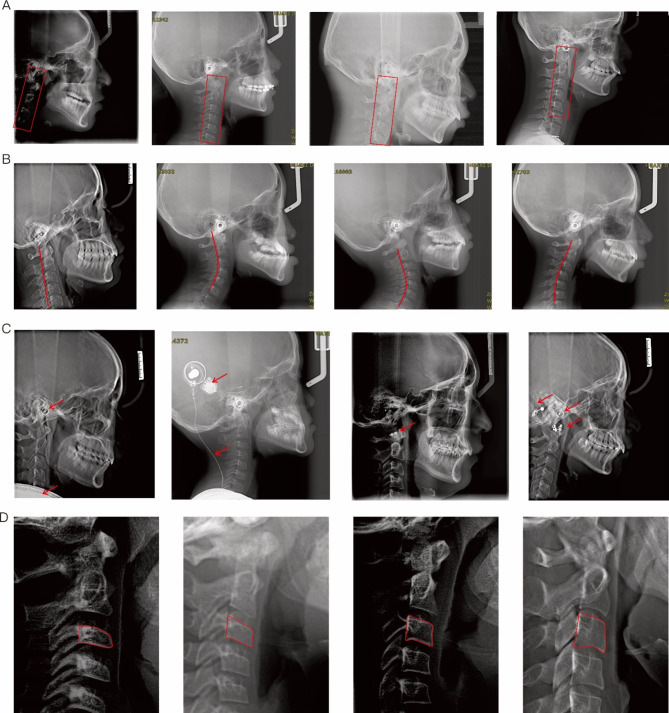

Methods: This study analyzed 2100 cephalometric images. The data distribution to an 8:1:1 for training, validation, and testing. The CVnet system was designed as a two-step method with a comprehensive evaluation of various regions of interest (ROI) sizes to locate 19 cervical vertebral landmarks and classify precision maturation stages. The accuracy of landmark localization was assessed by success detection rate and student t-test. The QCVM diagnostic accuracy test was conducted to evaluate the assistant performances of our system for six junior orthodontists.

Results: Upon precise calibration with optimal ROI size, the landmark localization registered an average error of 0.66 ± 0.46 mm and a success detection rate of 98.10% within 2 mm. Additionally, the identification accuracy of QCVM stages was 69.52%, resulting in an enhancement of 10.95% in the staging accuracy of junior orthodontists in the diagnostic test.